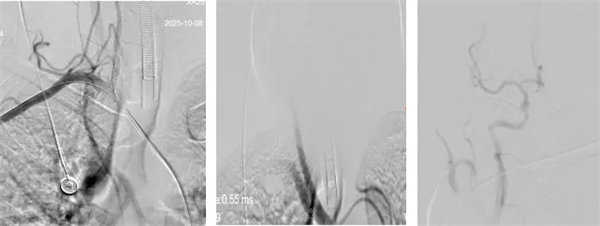

术中,介入团队精准定位血管闭塞部位,通过微导丝“探路”联合球囊扩张技术开通右侧椎动脉开口,造影椎开口残余狭窄60%。基底动脉血栓形成,基底动脉管腔狭窄55%,基底动脉尖堵塞,右侧大脑后动脉及小脑上动脉未见显影,左侧大脑后动脉P3以远闭塞。

席聪准确锁定患者基底动脉处血栓,采用抽吸取栓技术快速开通血管,成功取出堵塞部位2cm的血栓。再次造影示:右侧大脑后及双侧小脑上动脉再通,右侧大脑后动脉P3段以远闭塞,考虑慢性闭塞,推注替罗非班,血流明显加快。随后采用支架植入术开通右侧椎动脉开口处,术中影像显示:支架贴壁良好,无明显残余狭窄,颅内血管显影良好。